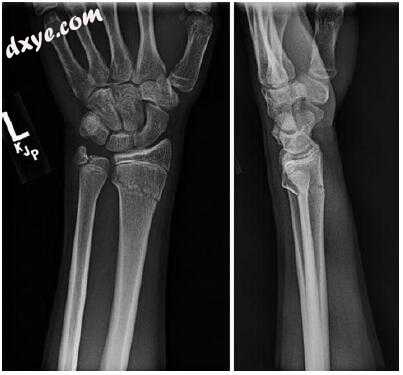

一名15岁的右撇子男性在打曲棍球时左手腕受到过度伸展的伤害。 当他与另一位球员相撞时发生了伤病。 他经历了立即的手腕疼痛,并且报告说他的手腕上有“砰砰的一声巨响”。 他向当地急诊室提交了X线片,其中X线片显示远端桡神经干骺端的双皮质横断骨(图16.1),远端骨折片的背侧角度大约为14°。 背侧皮质粉碎并且桡骨骨折线倾斜延伸至远端桡骨物理的5mm内。 还有相关的尺骨茎突骨折。 他否认了左手腕严重受伤或手术史。

图16.1一名15岁男性患者左腕超伸伤的初始X光